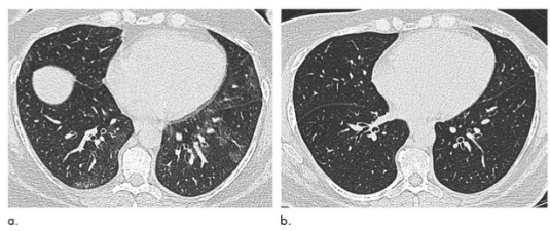

图1 51岁女性,(a)减肥手术前和(b)减肥31 kg后6个月(体重指数下降36.1%)肺部轴位平扫CT图像。术前可见的“马赛克征”在术后消失。